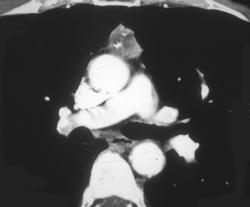

Diagnosis

Substernal Thyroid